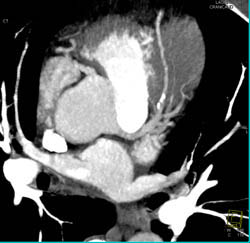

Nodal Branch Arises Directly Off Right Cusp